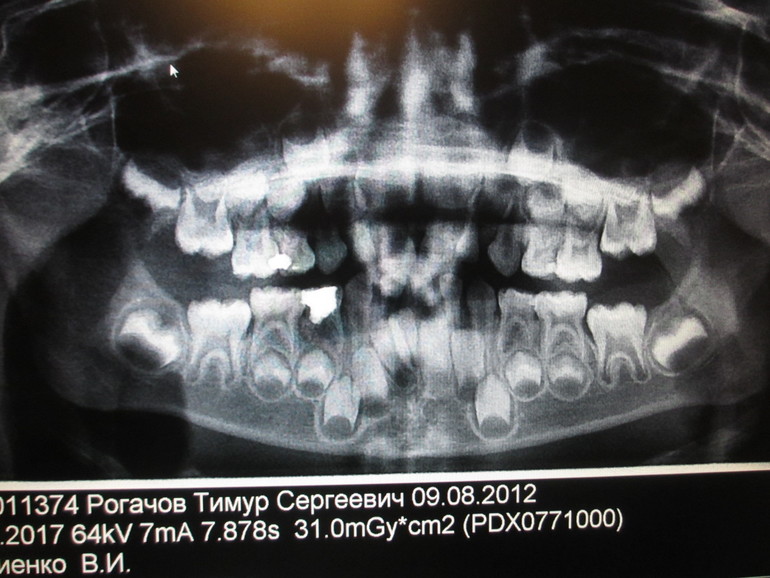

здравствуйте,очень нужна ваша консультация.У сына 5 лет только 3 молочных резца на нижней челюсти,по бокам сразу растут клыки ,если не считать.то даже не заметно.Сделали панорамный снимок,на нем видны 5 зачатков резцов,то ли один молочный,то ли 5 постоянных.Врач сказал,ждать смены зубов,а там будет видно.А я очень переживаю,что придется удалять или зубы будут какие то не такие,очень жду ваших рекомендаций.